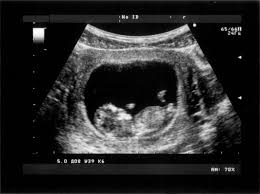

اشعة الحمل في الشهر الاول

متى يظهر كيس الجنين في السونار موضوع

متى يظهر الحمل في السونار ومتى يعتبر الحمل غير مكتمل